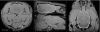

Rodent Brain Extraction Tool